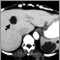

Liver and spleen cysts - CT scan

As many as half of people with PKD have cysts on the liver. A personal or family history of PKD increases your risk for the condition.

Polycystic kidney disease and associated cysts on the liver or other organs may be detected with the following tests: